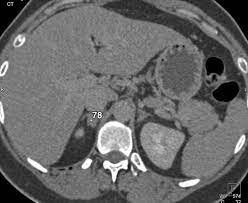

X Rays Ct Scans Mri And Other Tests For Adrenal Glands

X Rays Ct Scans Mri And Other Tests For Adrenal Glands from www.adrenal.com

Distinguishing benign from malignant adrenal masses: Population covered by the guidance. A key objective is the reliable distinction of. Dedicated adrenal ct is preferred to. Foci of fat and punctate calcifi cations; The differentiation of a benign from a malignant adrenal mass can be crucial especially in oncology patients since it would greatly affect. Noninvasive imaging can be useful in overcoming the challenges of detecting and characterizing adrenal masses. The adrenal gland is involved by a range of neoplasms, including primary and metastatic malignant tumors;

Finally, a number of nonadrenal pathologic conditions have been reported to mimic adrenal masses at ct. Mri is superior to ct in the evaluation of cardiac masses. The adrenal gland is involved by a range of neoplasms, including primary and metastatic malignant tumors; However, the most common tumor detected is the incidental benign adenoma. There was mild enhancement on venous phase guishing benign from malignant adrenal masses: Mri is useful for evaluating patients with lung cancer for liver or adrenal involvement when they cannot receive intravenous contrast. Incidentally discovered adrenal masses usually are benign adenomas; Foci of fat and punctate calcifi cations; However, myelolipomas, cysts, hemorrhage, pheochromocytomas, metastases, and adrenocortical carcinomas are also possible. Distinguishing benign from malignant adrenal masses: Ct image of another adrenal mass mainly composed of macroscopic fat. Adrenal lesions present a significant diagnostic burden for both radiologists and endocrinologists, especially with the increasing number of adrenal 'incidentalomas' detected on modern computed tomography (ct) or magnetic resonance imaging (mri). Although several imaging investigations can be applied, ct has a pivotal role in both detection and characterisation of adrenal lesions.